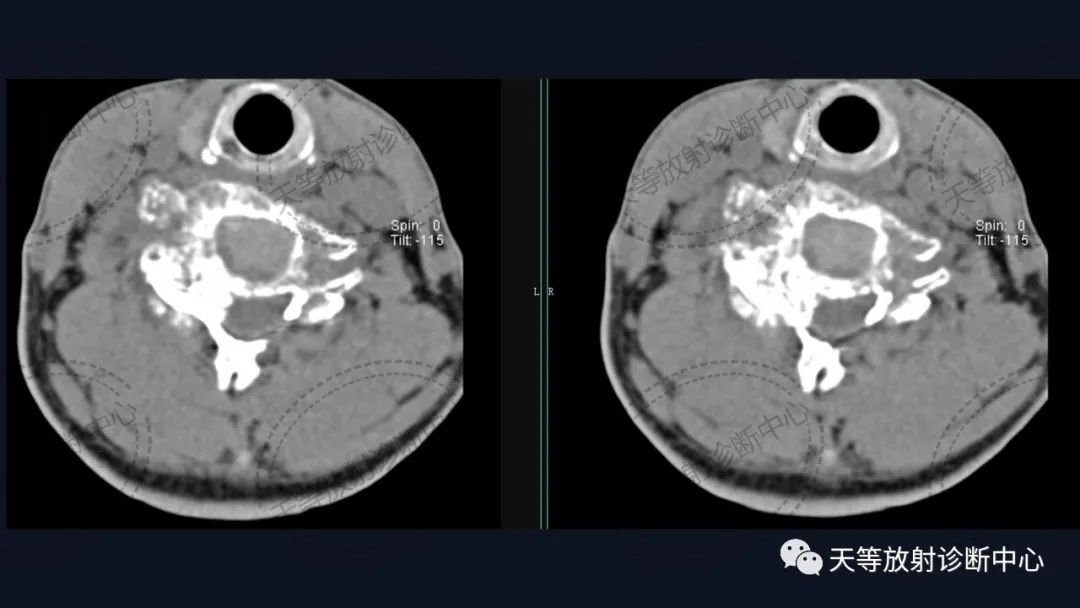

男性,54岁。男性,54岁。

软组织窗骨质破坏呈溶骨性、外生性生长,内部见大量钙化影。

骨质破坏呈溶骨性,大量钙化,肿块向外生长,局部突入椎管内。

术后内固定支架

肿瘤复发,椎旁分叶状软组织肿块,内部信号不均,混杂信号,高低信号不等,内见线状小叶间隔。

DWI信号较高,内部钙化灶呈散在泥沙样低信号灶。

病例1:上图:软骨肉瘤。CT显示椎管及其附件骨质溶骨性破坏,椎体周围软组织肿块并含大量钙化影,钙化呈斑片状、斑点状不定型。整个肿块外生性生长为主,局部突入椎管内。